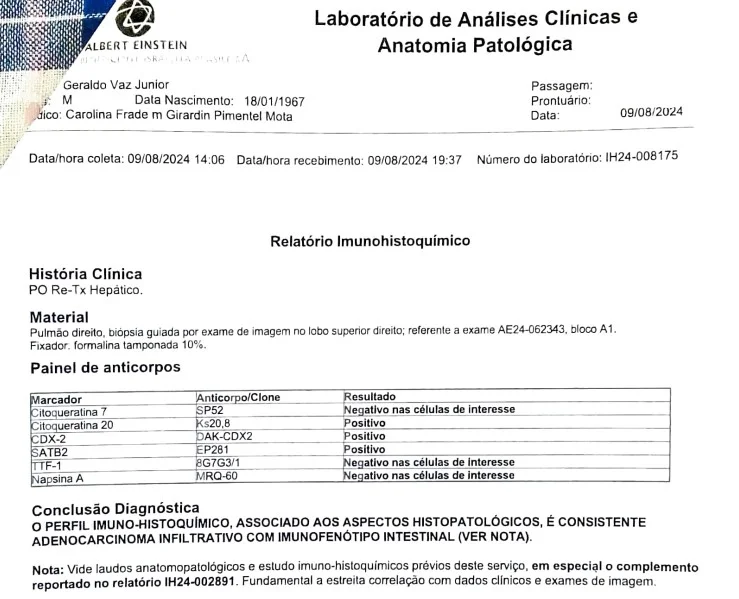

Relatório Imunohistoquímico ajuda os médicos a confirmar o tipo de câncer e descobrir de onde ele vem (em caso de metástase)

Sete meses depois, Júnior apresentou sintomas de alterações hepáticas e foi submetido a uma ressonância magnética, que apontou a presença de seis nódulos no fígado transplantado. Após biópsia, foi constatado que o achado se tratava de um adenocarcinoma – um dos tipos de câncer mais comuns em adultos, que pode se desenvolver no trato gastrointestinal, nos pulmões, no sistema reprodutor e em outros órgãos.

No início de agosto de 2024, veio mais um susto: foi detectada metástase no pulmão do paciente. A conclusão diagnóstica indicou um adenocarcinoma invasivo com as mesmas características das células cancerígenas do fígado transplantado.

“Isso sugere que a doadora já tinha um câncer que não foi detectado antes da doação, e pequenas células desse tumor estavam presentes no fígado transplantado”, explicou Caroline.